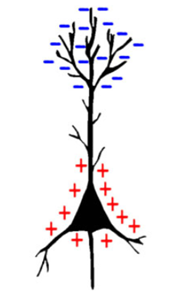

当神经元放电时,会形成偶极子,在突触处有较低的电压,在轴突处有较高的电压。如果是抑制性神经元,偶极子就会翻转,轴突的电压较低,突触的电压较高。是什么导致神经元内部发生这种电压偏移?钠离子(Na+)通道沿树突打开,产生大量正电子,此正电荷沿着轴突移动,打开更多的钠离子(Na+)通道,并导致电荷沿着轴突移动,在突触处放电,并释放神经递质。当成组的神经元一起放电时,它们为我们提供了足以从头皮进行测量的信号。我们只能使用EEG(大约直径的四分之一大小)来测量神经元簇。